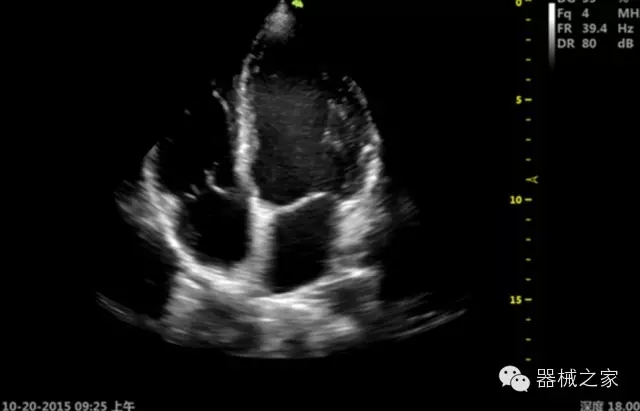

品牌:開立(SONOSCAPE)

公司簡介:

深圳開立生物醫(yī)療科技股份有限公司作為中國民族醫(yī)療產(chǎn)業(yè)的優(yōu)秀引導(dǎo)者,自成立伊始,一直致力于臨床醫(yī)療設(shè)備的研發(fā)和制造,產(chǎn)品涵蓋醫(yī)用數(shù)字超聲診斷系統(tǒng)、電子內(nèi)窺鏡系統(tǒng)、全自動(dòng)五分類血液細(xì)胞分析儀以及自主研發(fā)的探頭群。

官方網(wǎng)站:www.sonoscape.com.cn

經(jīng)典產(chǎn)品:S8EXP

臨床圖片賞析

產(chǎn)品特點(diǎn)

優(yōu)異的成像技術(shù)

·亞陣元技術(shù):獨(dú)有的亞陣元技術(shù),對獨(dú)立晶片做二次切割,減少旁瓣偽像,增加臨床診斷的準(zhǔn)確性;

·μ-Scan微米成像技術(shù):開立獨(dú)有的μ-Scan技術(shù),還原出真實(shí)細(xì)膩、層次對比優(yōu)異的二維圖像;